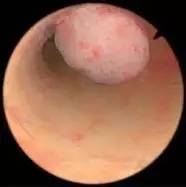

宫腔镜下息肉切除术是最主要的治疗方式,手术安全性高,并不推荐盲目刮宫。

三四线城市的医院不是特别缺床位,她还有个亲戚是当地医院的工会主席,顺风顺水地住院,没几天就在静脉麻醉下进行了子宫内膜息肉的电切手术(TCRP)。

术后该怀孕了,结果连着仨月没来月经,她慌了神儿,做B超怀疑宫腔粘连。

实际上,息肉是子宫内膜长出来的,切除手术不会累及子宫肌层,理论上不会造成宫腔粘连。手术后的粘连多是继发感染,或者医生的电切环没把握好深度,切深了,伤害到子宫肌层,才会粘连,属于少见并发症。